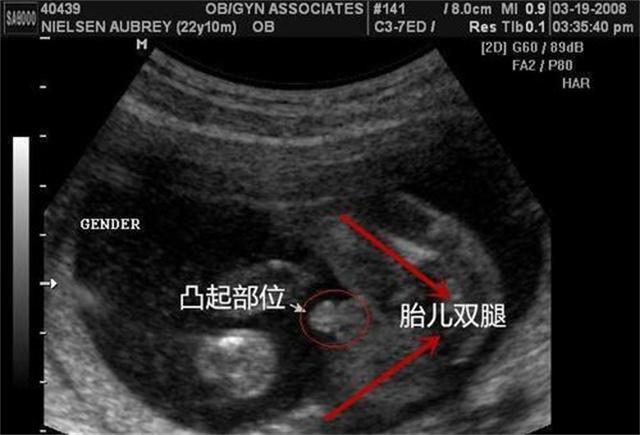

Deng Bo a également déclaré qu'il est certain que, que ce soit dans les hôpitaux chinois ou occidentaux, dans le diagnostic de la grossesse dans les critères cliniques, il n'y a pas de "diagnostic du test de grossesse par pouls", l'étalon-or pour le diagnostic de la grossesse étant de trois : test d'urine, tests sanguins et échographie.

Le diagnostic par pouls était donc relativement le moyen de diagnostic le plus précis dans les temps anciens où il n'y avait pas autant de tests qu'aujourd'hui. À l'époque moderne, il existe de nombreux moyens de diagnostiquer la grossesse, tels que les tests d'urine, les tests sanguins, l'échographie, etc., qui peuvent être utilisés comme simple test préliminaire, puis comme moyen plus précis de déterminer le résultat final. Le diagnostic par le pouls de la médecine traditionnelle peut être utilisé à l'heure actuelle comme l'un des moyens de détection préliminaire précoce, avec l'échographie pour la confirmation finale.

Bien que l'anneau n'ait pas été réglé, les résultats devraient être, il va sans dire, la précision médicale moderne est plus élevée, parce que le moderne a été en mesure de pénétrer directement dans le corps humain, il n'y a pas de sac gestationnel et le cœur du fœtus n'est pas à un coup d'œil, et au début de la grossesse, le cœur du fœtus est encore très faible lorsque le sac gestationnel peut être observé par le diagnostic hormonal de la grossesse ou non. La méthode traditionnelle consistant à s'appuyer sur le diagnostic par le pouls présente naturellement de nombreuses lacunes et, en raison des différences d'expérience personnelle, il est difficile de parvenir à la même conclusion pour différentes personnes, et il est également difficile de la comparer avec les moyens diagnostiques et thérapeutiques modernes. Dans le diagnostic d'autres maladies, le diagnostic par le pouls conduira également à des conclusions et à des traitements différents selon les médecins, ce qui fait que le traitement traditionnel manque de normes uniformes, que les personnes extérieures semblent se moquer du monde, mais qu'en fait, même dans la médecine moderne, une maladie ayant plusieurs types de traitement est également très courante.

En outre, pour éviter les faux positifs, outre le contrôle du taux de gonadotrophine chorionique humaine dans le sang, d'autres tests complémentaires sont parfois utilisés pour éviter les erreurs de diagnostic, tels que l'échographie en mode B, l'échographie Doppler, etc.